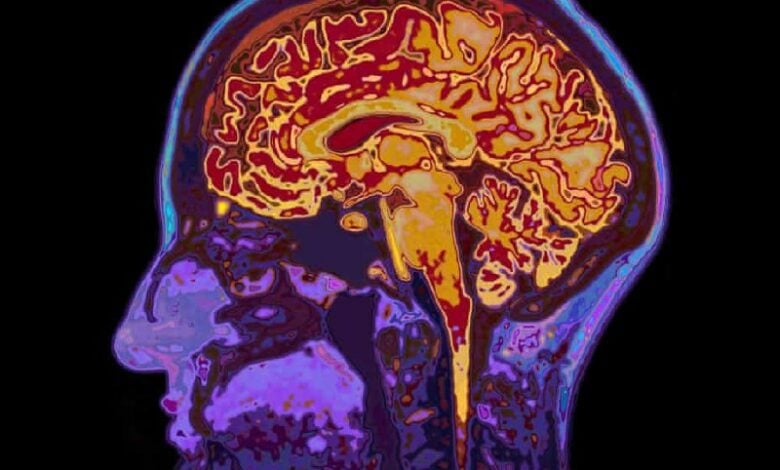

New research has revealed that brief lapses in attention, often triggered by sleep deprivation, coincide with waves of fluid moving out of the brain, as reported by The Guardian. Scientists at the Massachusetts Institute of Technology (MIT) found that when focus drops, cerebrospinal fluid pulses out of the brain and returns once attention resumes—suggesting a deeper biological process behind “zoning out.”

The study, published in Nature Neuroscience, involved 26 volunteers who underwent brain scans using EEG and fMRI after both normal sleep and a night without rest. Participants reacted significantly slower to visual and auditory cues when sleep deprived. The researchers observed that just after a lapse in focus, cerebrospinal fluid was expelled from the brain—a pattern similar to deep sleep, where such waves help clear metabolic waste.

Physiological signs accompanied the process, with pupils shrinking about 12 seconds before the fluid movement and heart rate and breathing also slowing. Experts say the findings show that the brain may temporarily “switch off” to perform necessary maintenance, even when awake. Scientists described these short lapses as structured biological events that might protect the brain by giving it brief moments of rest.